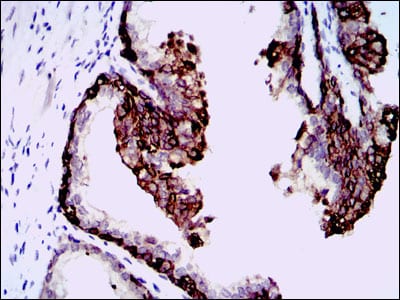

Immunohistochemical analysis of paraffin-embedded human prostate tissues using NT5DC3 mouse mAb with DAB staining